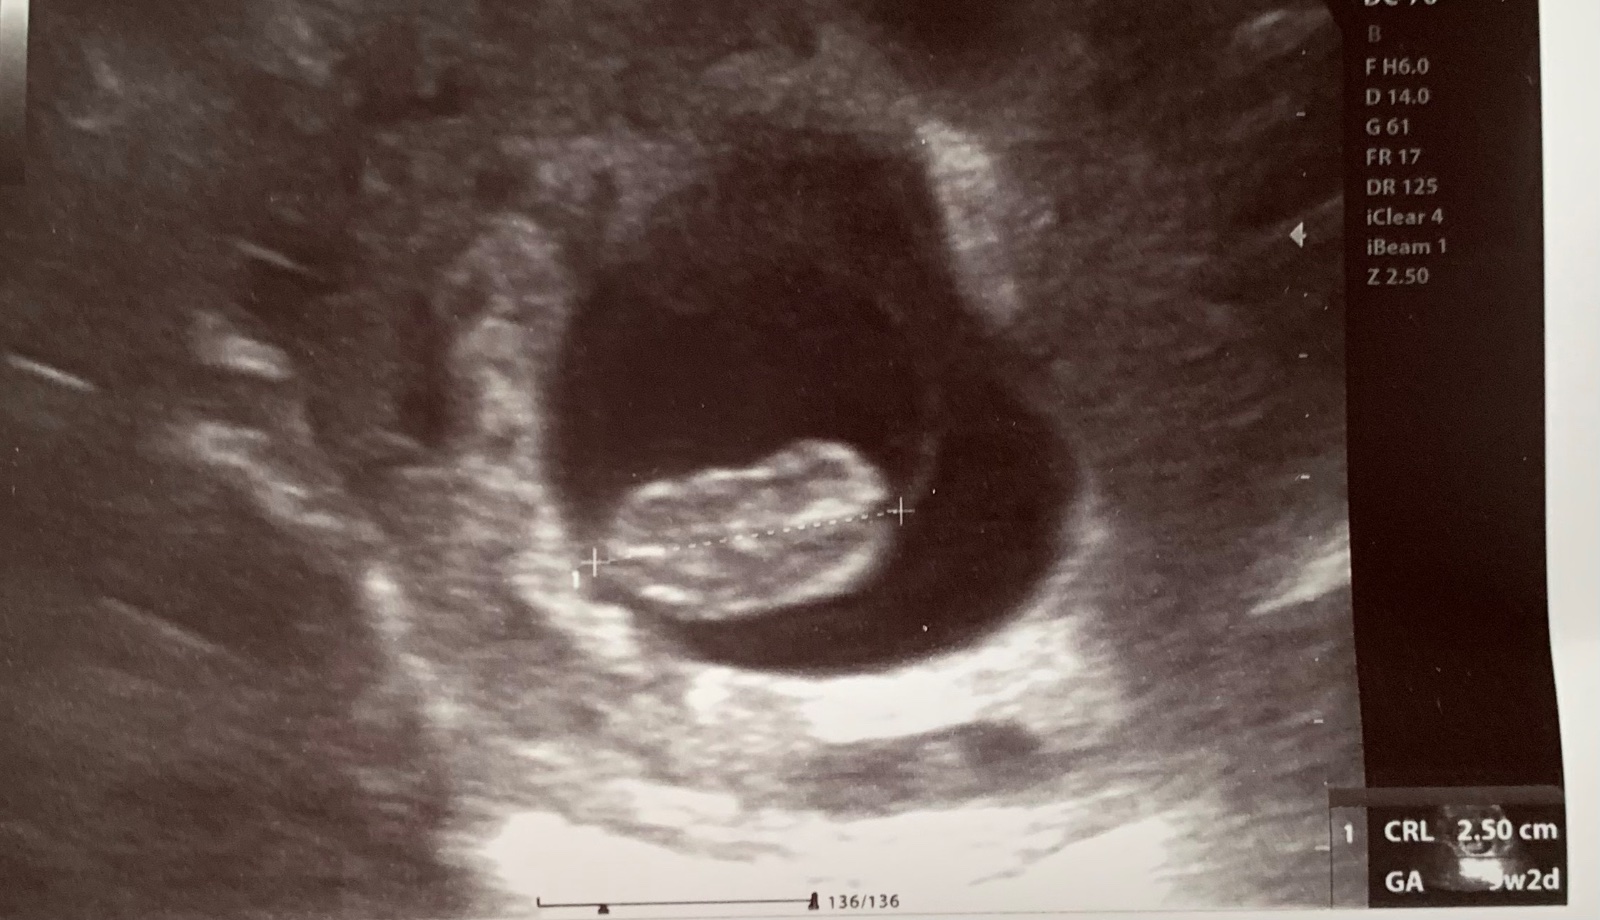

Oplatí sa absolvovať 3D ultrazvuk alebo 4D ultrazvuk?

A ako prebiehajú screeningy v 1. a v 2. trimestri?